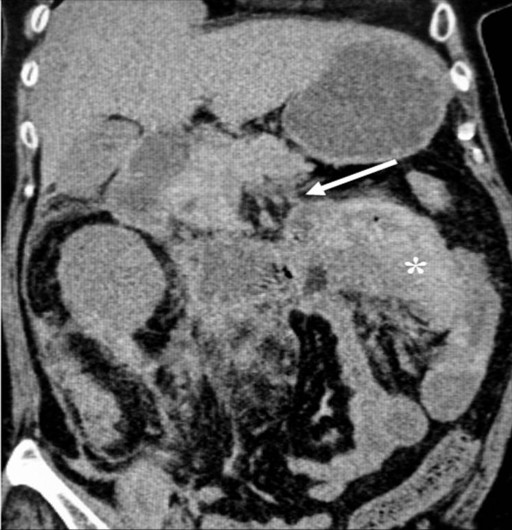

She was immediately referred to the surgical service and an urgent computed tomography (CT) scan was carried out. This showed a thickened jejunal loop consistent with a hematoma, a dilated fluid-filled proximal duodenum and stomach, a solitary gallstone and a swollen pancreatic head and body with peripancreatic fat streaking, consistent with acute pancreatitis (Figure 1). The jejunal hematoma was located in the proximal jejunum and extended for approximately 10 cm. Close inspection of the pancreatic and common bile duct did not reveal any abnormalities, such as dilatation, stones or pancreas divisum. There were no abnormalities, such as calculus, seen in the urinary system to account for the hematuria. Laboratory investigations revealed an elevated serum amylase level of 1,962 IU/L (reference range: 0-120 IU/L) and normal liver function with the exception of elevated serum bilirubin of 78 μmol/L (reference range: 0-34 μmol/L). A review of her previous liver function tests carried out when she had previously complained of intermittent mild epigastric pain had shown intermittent cholestatic profiles which had resolved spontaneously. Unfortunately, she was not evaluated with an ultrasound scan of the abdomen. Given the history of abdominal pain characteristic of biliary colic which had preceded the abdominal distension, a diagnosis of acute gallstone pancreatitis complicated by a jejunal hematoma was made. This was despite the minimally abnormal liver profiles on admission.

Figure 1. Reconstructed CT scan showing a jejunal hematoma (asterisk) and an irregular slightly swollen pancreatic body with peripancreatic fat streaking (arrow), dilated fluid-filled duodenum and stomach secondary to jejunal obstruction. |